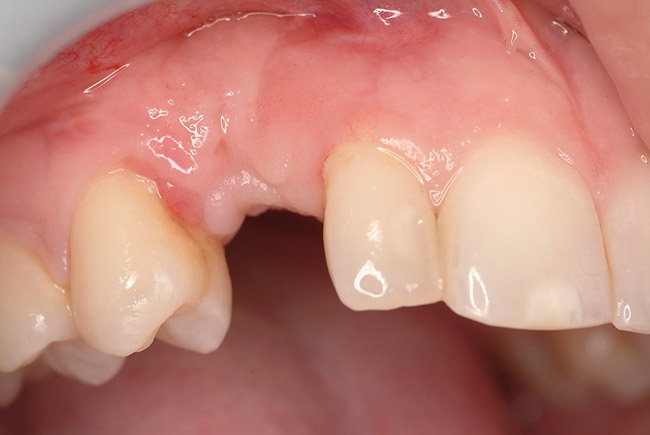

A 26-year-old woman presented with a history of trauma combined with an impacted maxillary right canine (No. 6), which was extracted in early childhood. Following two courses of orthodontic therapy—one in her early teens and the second in early adulthood—the area had reportedly been grafted approximately 9 months prior to her initial presentation to the author’s private periodontal practice. Clinically, the edentulous site appeared healthy, with significant keratinized mucosa in the canine position (Figure 1). A cone-beam CT scan revealed severe horizontal bone deficiency in the proposed implant position (Figure 2). Adequate bone height for implant placement was evident; however, the thinnest portion of the ridge measured approximately 0.45 mm in width. It was proposed that an augmentation be performed to facilitate implant placement, which the patient accepted.

Figure 1  In Case 1, the patient’s edentulous site appeared healthy, with significant keratinized mucosa in the canine position.

Figure 1